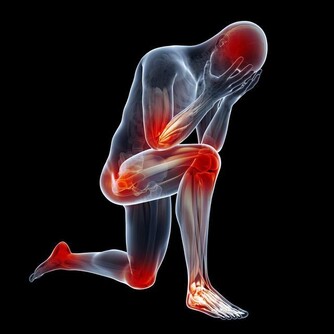

腎臟已經出現損傷,身體會有這幾個表現

1、精神不振、疲勞、乏力,還會出現無緣由的腰酸背痛。

2、胃口不好、噁心嘔吐。

3、晨起眼瞼或顏面水腫,下肢水腫,且按壓後凹陷部位無法馬上恢復。

4、小便有泡沫,久久都不消。

5、尿量變多或變少,都可能是腎臟疾病。